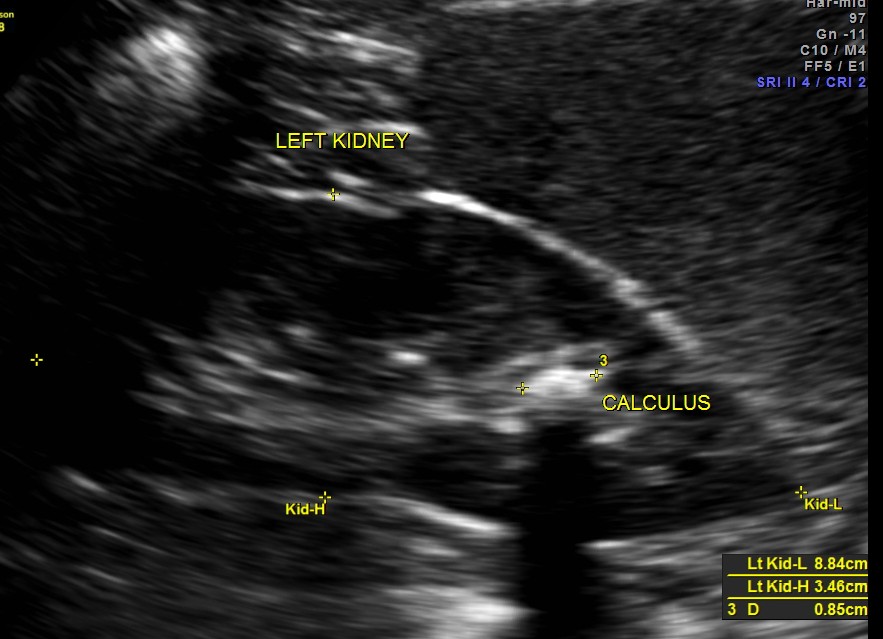

The left kidney showed a calculus.